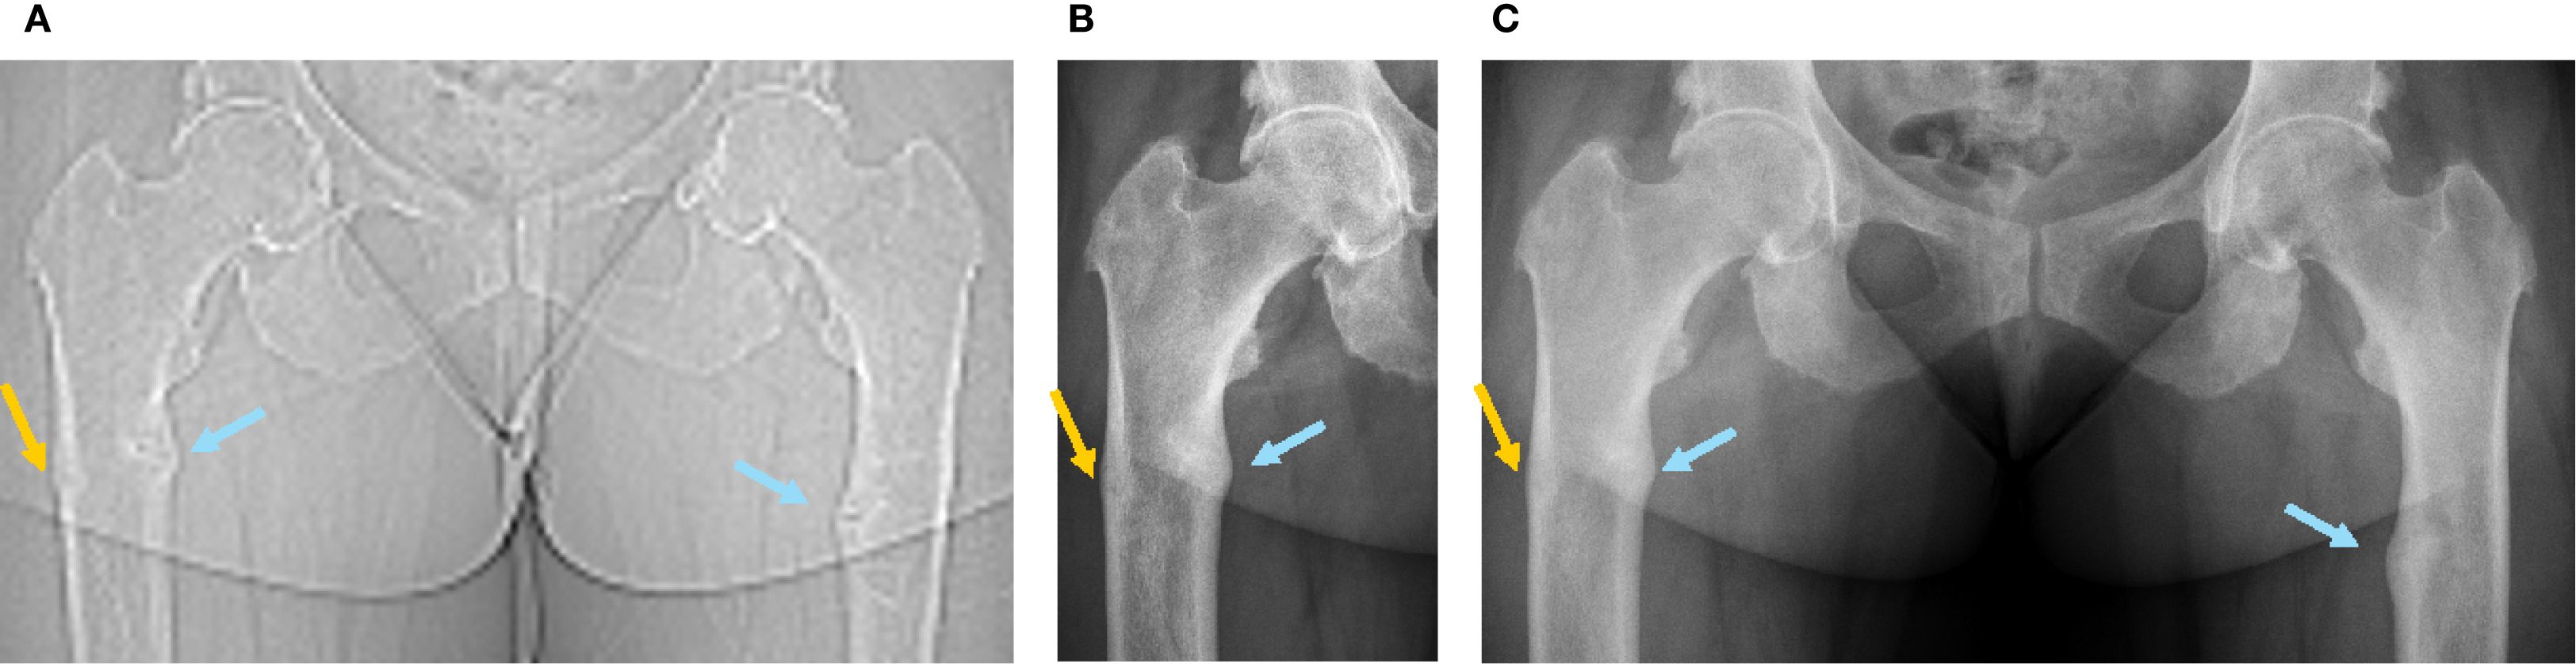

A 36-year-old woman was followed at our consultation for XLH due to a de novo heterozygote variant on the exon 16 of the PHEX gene. First symptoms that appeared during childhood required orthopedic surgeries of both tibia for bowing legs despite early introduction of conventional treatment; she developed coxa vara and profunda bilaterally. After a period of bad adherence to phosphate substitution due to digestive secondary effects, she developed femoral shaft bilateral pseudofractures of the medial cortical (incomplete cortical fracture on radiography associated with periosteal reaction) at ages 24 (left) and 26 (right) years (Figures 1A, 2A, blue arrows), which were managed conservatively with good initial response thanks to improved treatment observance after a phosphate formula change, and weight discharge. They however did not completely heal, with occasional transient increase in pain, and progressive appearance of joint stiffness, depending on intermittent irregular observance.

Figure 1. Radiographic images of the femoral fractures before and after introduction of burosumab treatment (first burosumab injection: 04.01.2021). (A) SPECT-CT topogram before introduction of burosumab treatment (16.09.2020). (B) Five weeks after first burosumab injection (12.02.2021). (C) Three and a half months after first burosumab injection (23.04.2021).

Blood exams showed slightly decreased phosphate serum concentrations (0.73 mmol/L; N 0.80-1.40), with alkaline phosphatase and 25-OH vitamin D in the normal range and mild secondary hyperparathyroidism (Table 1, first row). Renal function showed a normal result (creatinine 50 µmol/l, N 44-80). As expected, iFGF23 was elevated (Table 1), and there was renal phosphate wasting. SPECT-CT showed a new threatening fracture of the lateral cortical of the right femur (Figures 1A, 2A, orange arrow) and highly increased activity on the two already known ones. Since bowing legs favor insufficiency fractures, orthopedist advise was to realign the femurs to decrease constraints and risk of spontaneous completion. At this point, a request for reimbursement of burosumab, which was available in Switzerland since May 2020, was transitorily accepted by her health insurance. The patient received the first dose on 04.01.2021, after 2 weeks of conventional treatment washout. It was administered every 4 weeks with incremental doses in order to approach the lower limit of normal (LLN) phosphate serum concentration 2 weeks after an injection.

The most remarkable effects were related to the improvement of the patient’s symptoms. The function and pain questionnaires evaluated respectively by the WOMAC scores showed a rapid improvement in pain, stiffness, and disability (Figure 3). The patient stopped regularly taking painkillers 2 months after the beginning of burosumab, and she was able to resume part-time work. These findings were strictly related to radiological improvement: the fracture traits healed after two doses of burosumab (Figures 1B, C). On October 2021, the orthopedics renounced to the surgery because of closure of fracture trait and in part realignment of the femur.